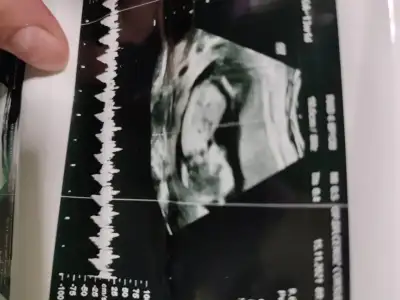

Rica etsem tahminde bulunurmusunuz kndini gostrmedi bebegim snra doktor bakti kordon vardı 13+3gunluk ultrason resmi

IMG-20211031-WA0002.webp